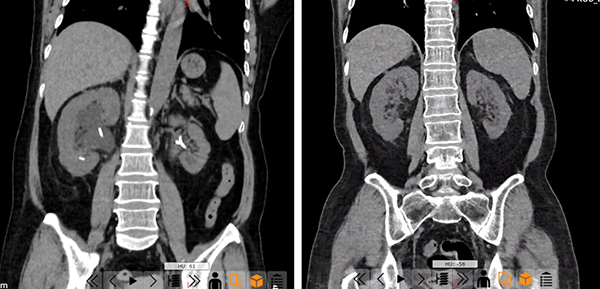

李女士治疗前后CT对比